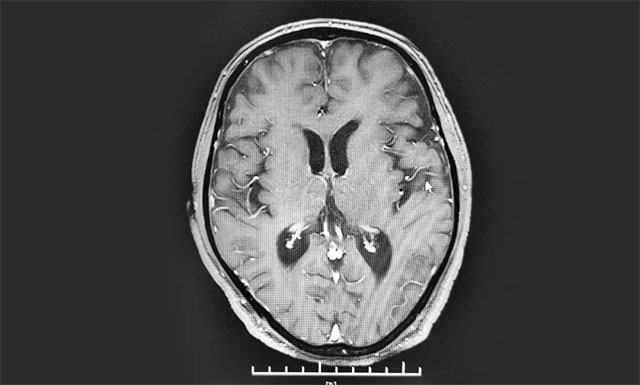

▲ 复查时病灶明显缩小

今年8月下旬,患者经出院休养后再次来院复查,病灶明显缩小。看到复查结果,患者紧紧握住了医生的手,感激之情溢于言表。